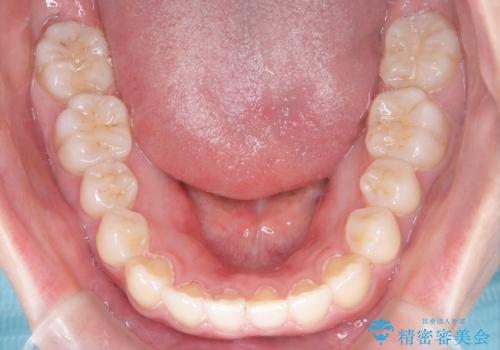

- 患者様は歯並びの乱れを気にされて来院されました。特に小臼歯の捻転(ねじれ)が強く、見た目だけでなく噛み合わせにも影響がありました。できるだけ目立たない方法を希望されていたため、インビザライン(マウスピース矯正)を基本としつつ、より精密な動きが必要な部分にはワイヤー矯正を併用する計画を立てました。また、小臼歯の捻転については**部分矯正(MTM:Minor Tooth Movement)**を取り入れ、効率的に改善を目指しました。

まず、全体の歯並びを整えるためにインビザラインを使用し、徐々に理想的な位置へと歯を移動させました。一方で、ねじれの強い小臼歯に対しては、**部分的なワイヤー矯正(MTM)**を行い、より精密なコントロールを実施。約2年の治療期間を経て、歯並びと噛み合わせが整い、見た目の美しさだけでなく、機能的な改善も達成しました。患者様からは「自然な仕上がりで、自信を持って笑えるようになった」と喜びの声をいただきました。